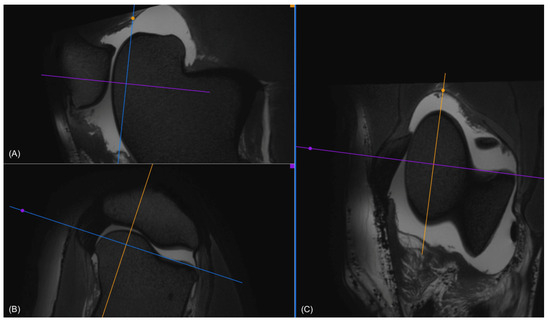

Figure 1. (A) Sagittal, (B) transverse, and (C) dorsal view in 3D VIEW T2-weighted images of a stifle, where the regions of interest (ROIs) were determined for the medial trochlear ridge. In the transverse view (B), the dorsal plane (blue) was oriented to be parallel to the joint space. In the dorsal view (C), the sagittal plane (yellow) was oriented according to the long axis of the medial ridge. This was repeated for lateral and axial measurements by orienting the sagittal plane (yellow), according to the long axis of the lateral ridge and the trochlear groove, respectively.